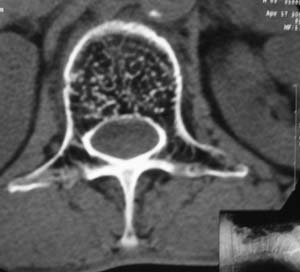

以下是引用余辉在2008-4-27 17:12:00的发言:[br]骨质疏松伴病理性压缩性骨折,椎骨骨松质密度减低,椎体骨小梁稀疏且普遍呈火柴头样改变,椎体无膨胀,无软组织肿块

以下是引用mzh123在2008-4-27 19:33:00的发言:[br]除压缩骨折表现外 还有许莫氏结节改变

以下是引用随光逐影在2008-4-27 21:29:00的发言:[br]除压缩性骨折外,还有许莫氏结节及骨质疏松表现。